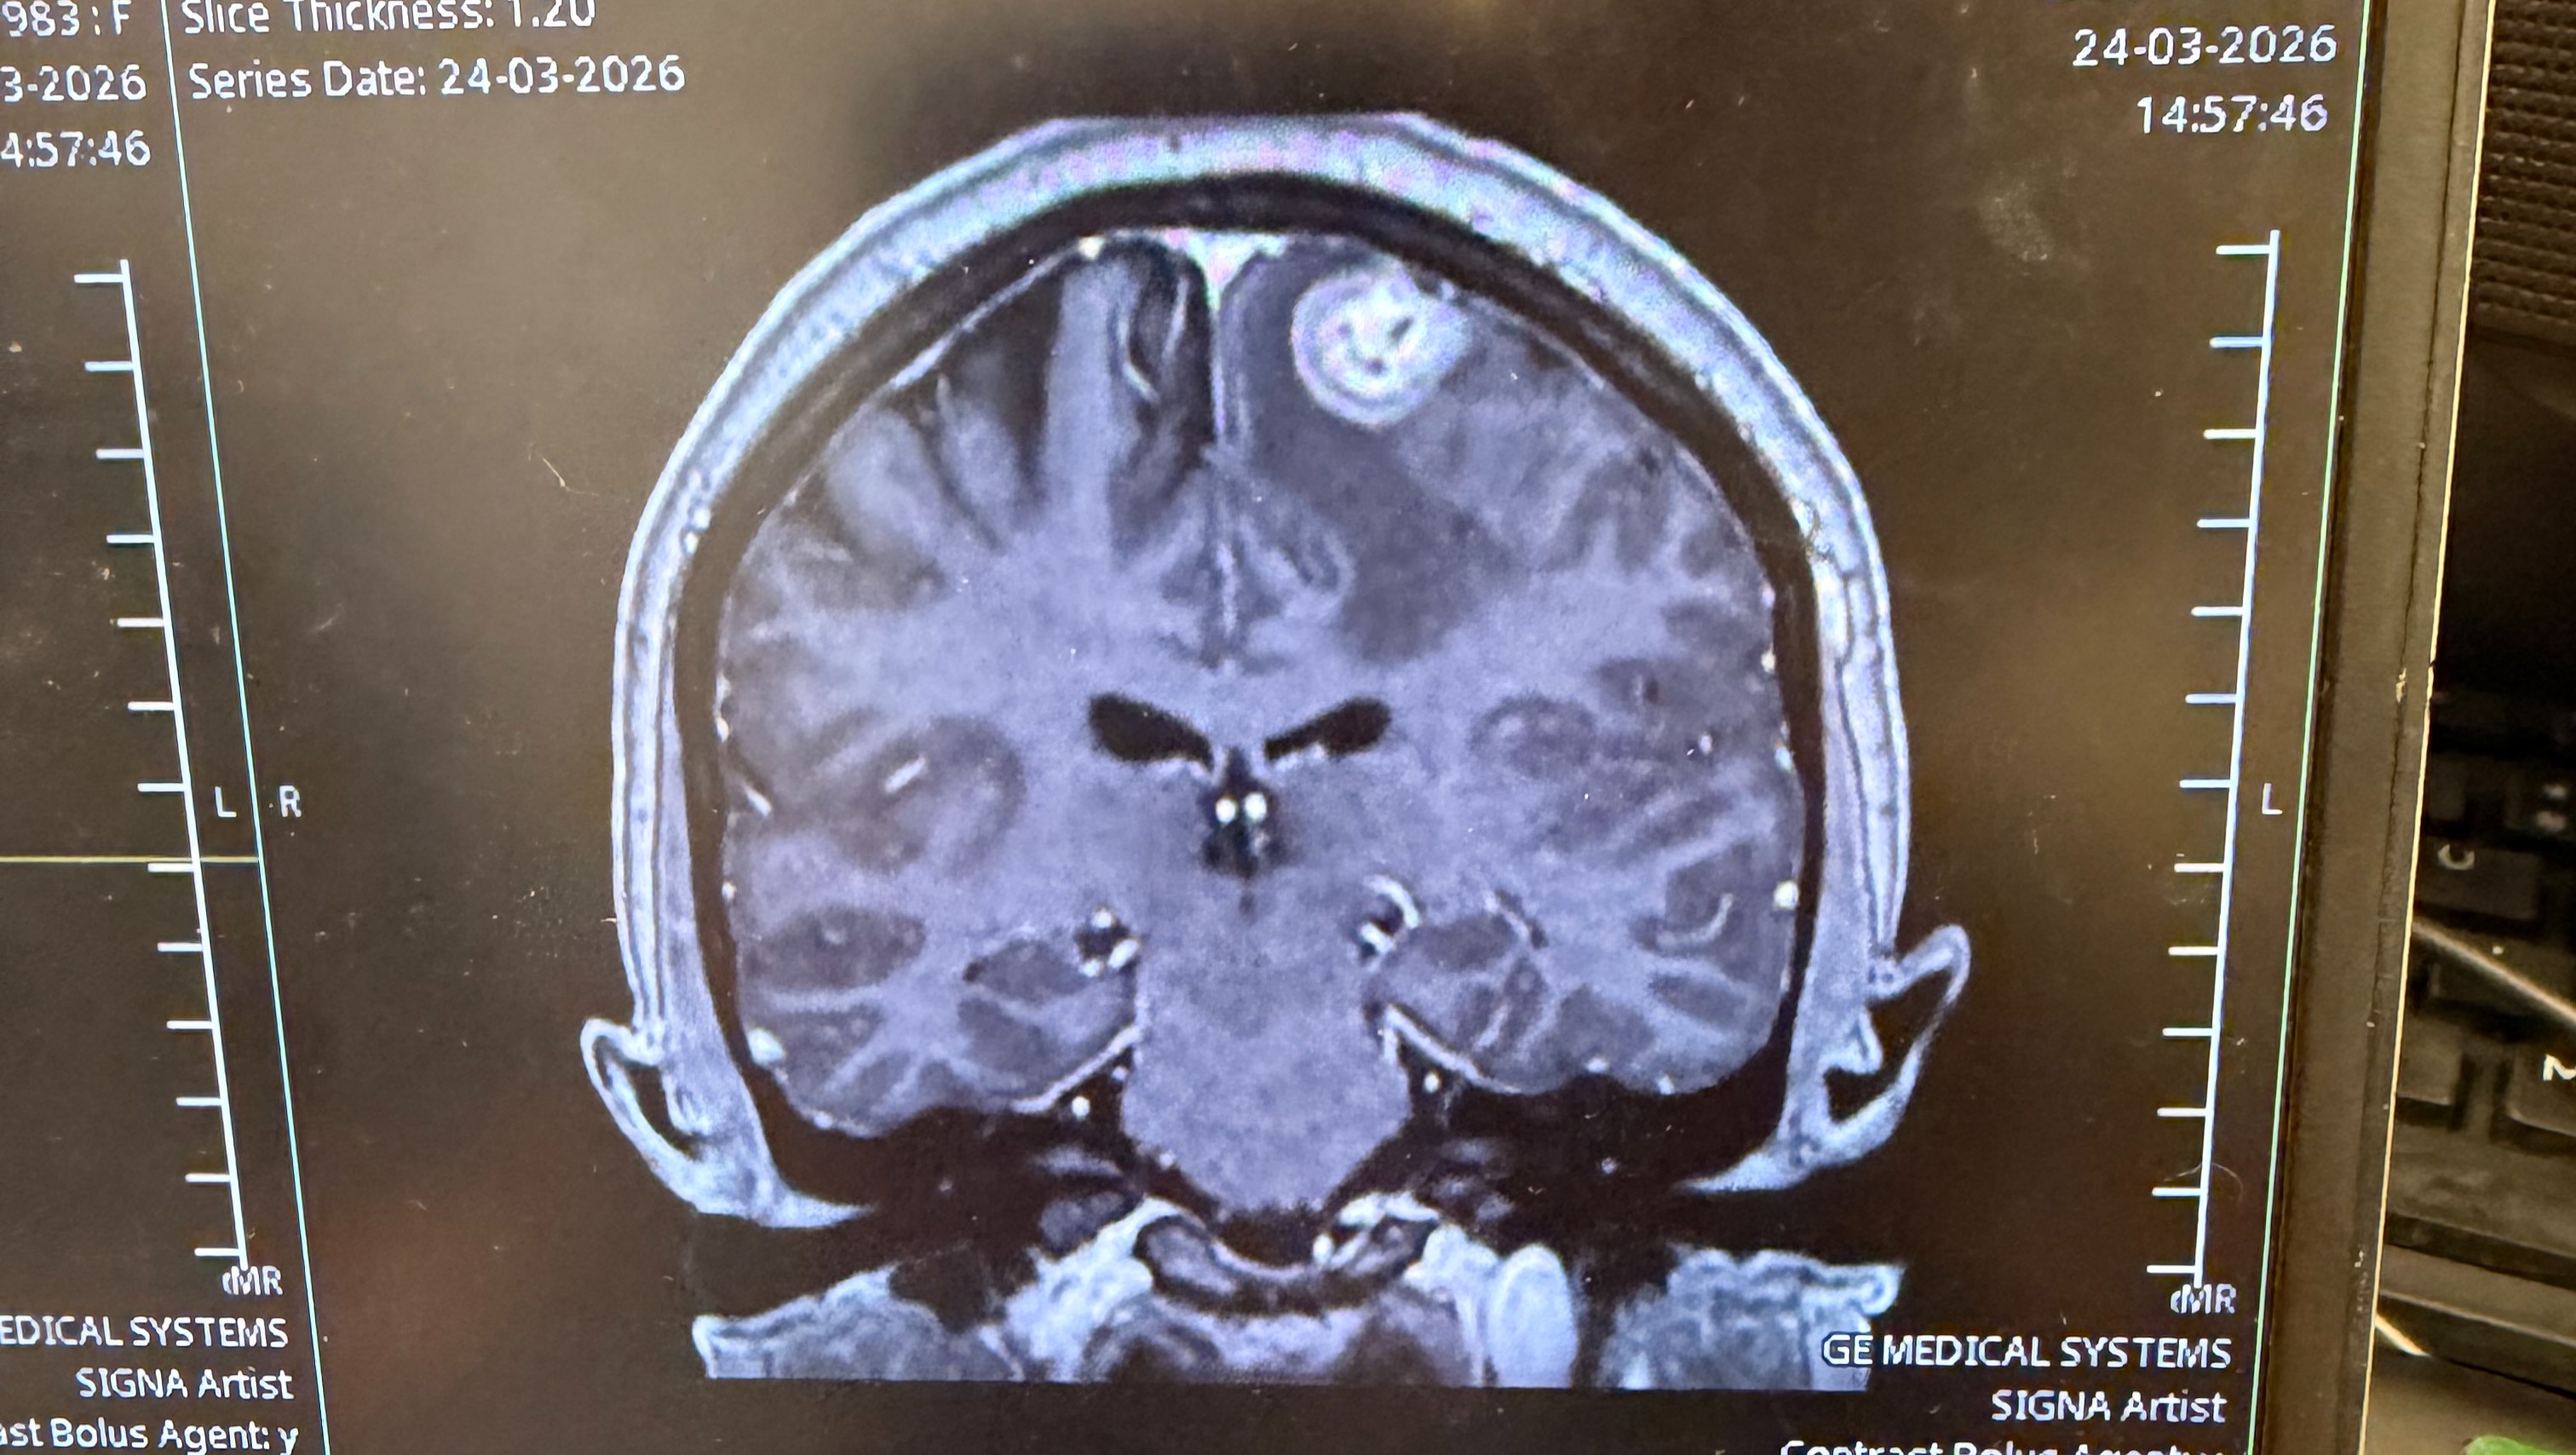

The devastating moment we learnt the cancer had spread to her brain and liver.

Katie undergoing intensive treatment to fight against cancer.